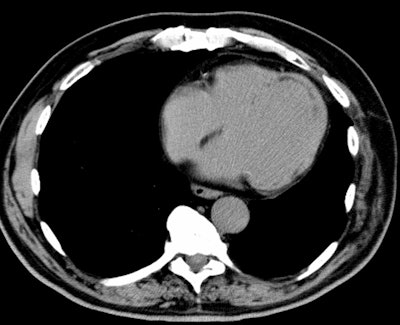

CT:

On dynamic imaging, an acute area of myocardial infarction will demonstrate decreased contrast enhancement.

.Massive acute MI: Contrast CT demonstrates a massive acute MI with extensive areas of decreased enhancement involving the anterior, lateral, and septal walls (black arrows). Inferior wall is enhancing normally. Note bright epicardial enhancement in the infarcted regions (white arrows).